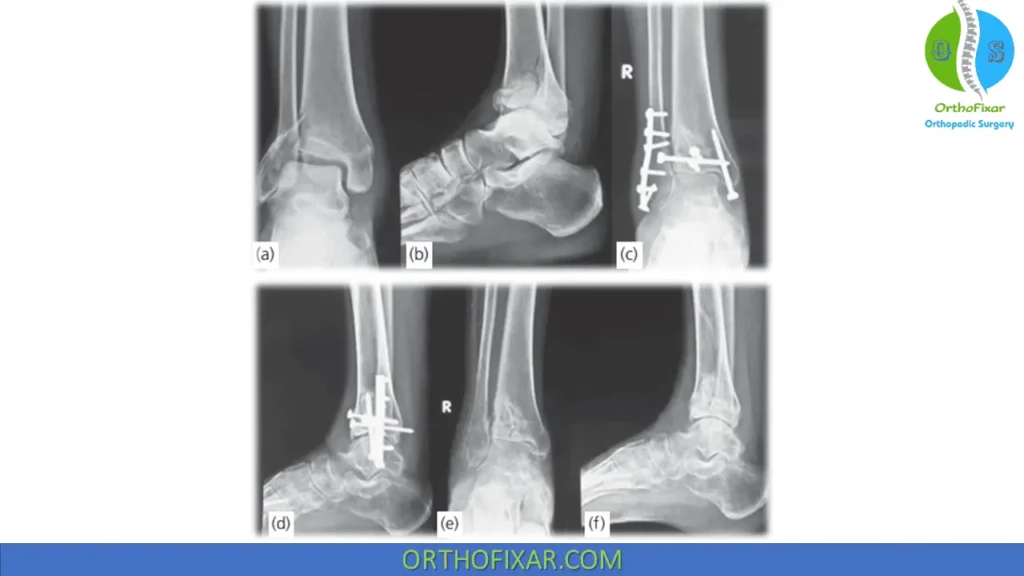

Principles of ORIF:

- Anatomic reduction and absolute rigid fixation of articular surface

- Preserve tibial length.

- Reconstruction of metaphyseal shell

- Bone grafting of metaphyseal defects

- Reattachment of metaphysis to diaphysis: Bridge plating technique is appropriate, without requirement to achieve anatomic reduction. Restoration of length, alignment, and rotation are critical.